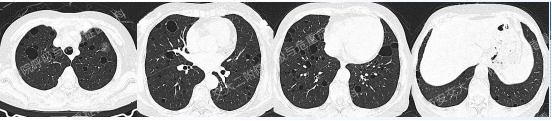

上图与Case 2比较相似,所以诊断LAM没有问题,还需进一步排查系散发型还是结节性硬化症累及。

影像学评估发现患者多系统受累(肝脏错构瘤、双肾血管平滑肌脂肪瘤、颅脑多发异常信号结节)。追问病史,患者本人无皮疹、癫痫及智力低下;患者儿子有面部皮脂腺瘤,无癫痫及智力低下,胸腹部CT未见异常,皮肤科已确诊结节性硬化症;患者女儿面容及智力均正常;建议患者进一步行TSC基因检测,结果回报TSC2突变,结节性硬化症诊断明确。

患者尝试口服西罗莫司2mg/日,消化道难以耐受,减至1mg/日,仍有恶心等不适,自行停药,不愿再尝试药物治疗,目前随访观察中。